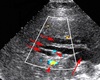

Bile Duct Obstruction oObstruction causes direct interference with bile flow oObstruction from intrinsic or extrinsic cause (stones, tumors, and strictures) oCan be intrahepatic or extrahepatic location oIntrahepatic can be caused by primary sclerosing cholangitis (PSC), or space-occupying liver mass. oObstruction at porta hepatis can be due to cholangiocarcinoma, PSC, GB cancer, or metastatic tumors. oBiliary obstruction at pancreas includes pancreatic cancer, pancreatitis, choledocholithiasis, or cholangiocarcinoma. oPrevious obstruction or inflammation with loss of elasticity or ampullary dysfunction may cause duct to dilate. Types: -complete common bile duct obstruction -incomplete obstruction -extrinsic -intrinsic

Aka parallel channel sign, representing dilated duct running anterior to its accompanying portal vein or hepatic artery. Irregular jagged, walls and branching patterns of ducts, compared to smooth walls and smooth verifications of portal venus system. Stellated confluence of dilated ducts converging toward the porta hepatis.

Double-barreled shotgun

56

Double barrel shotgun